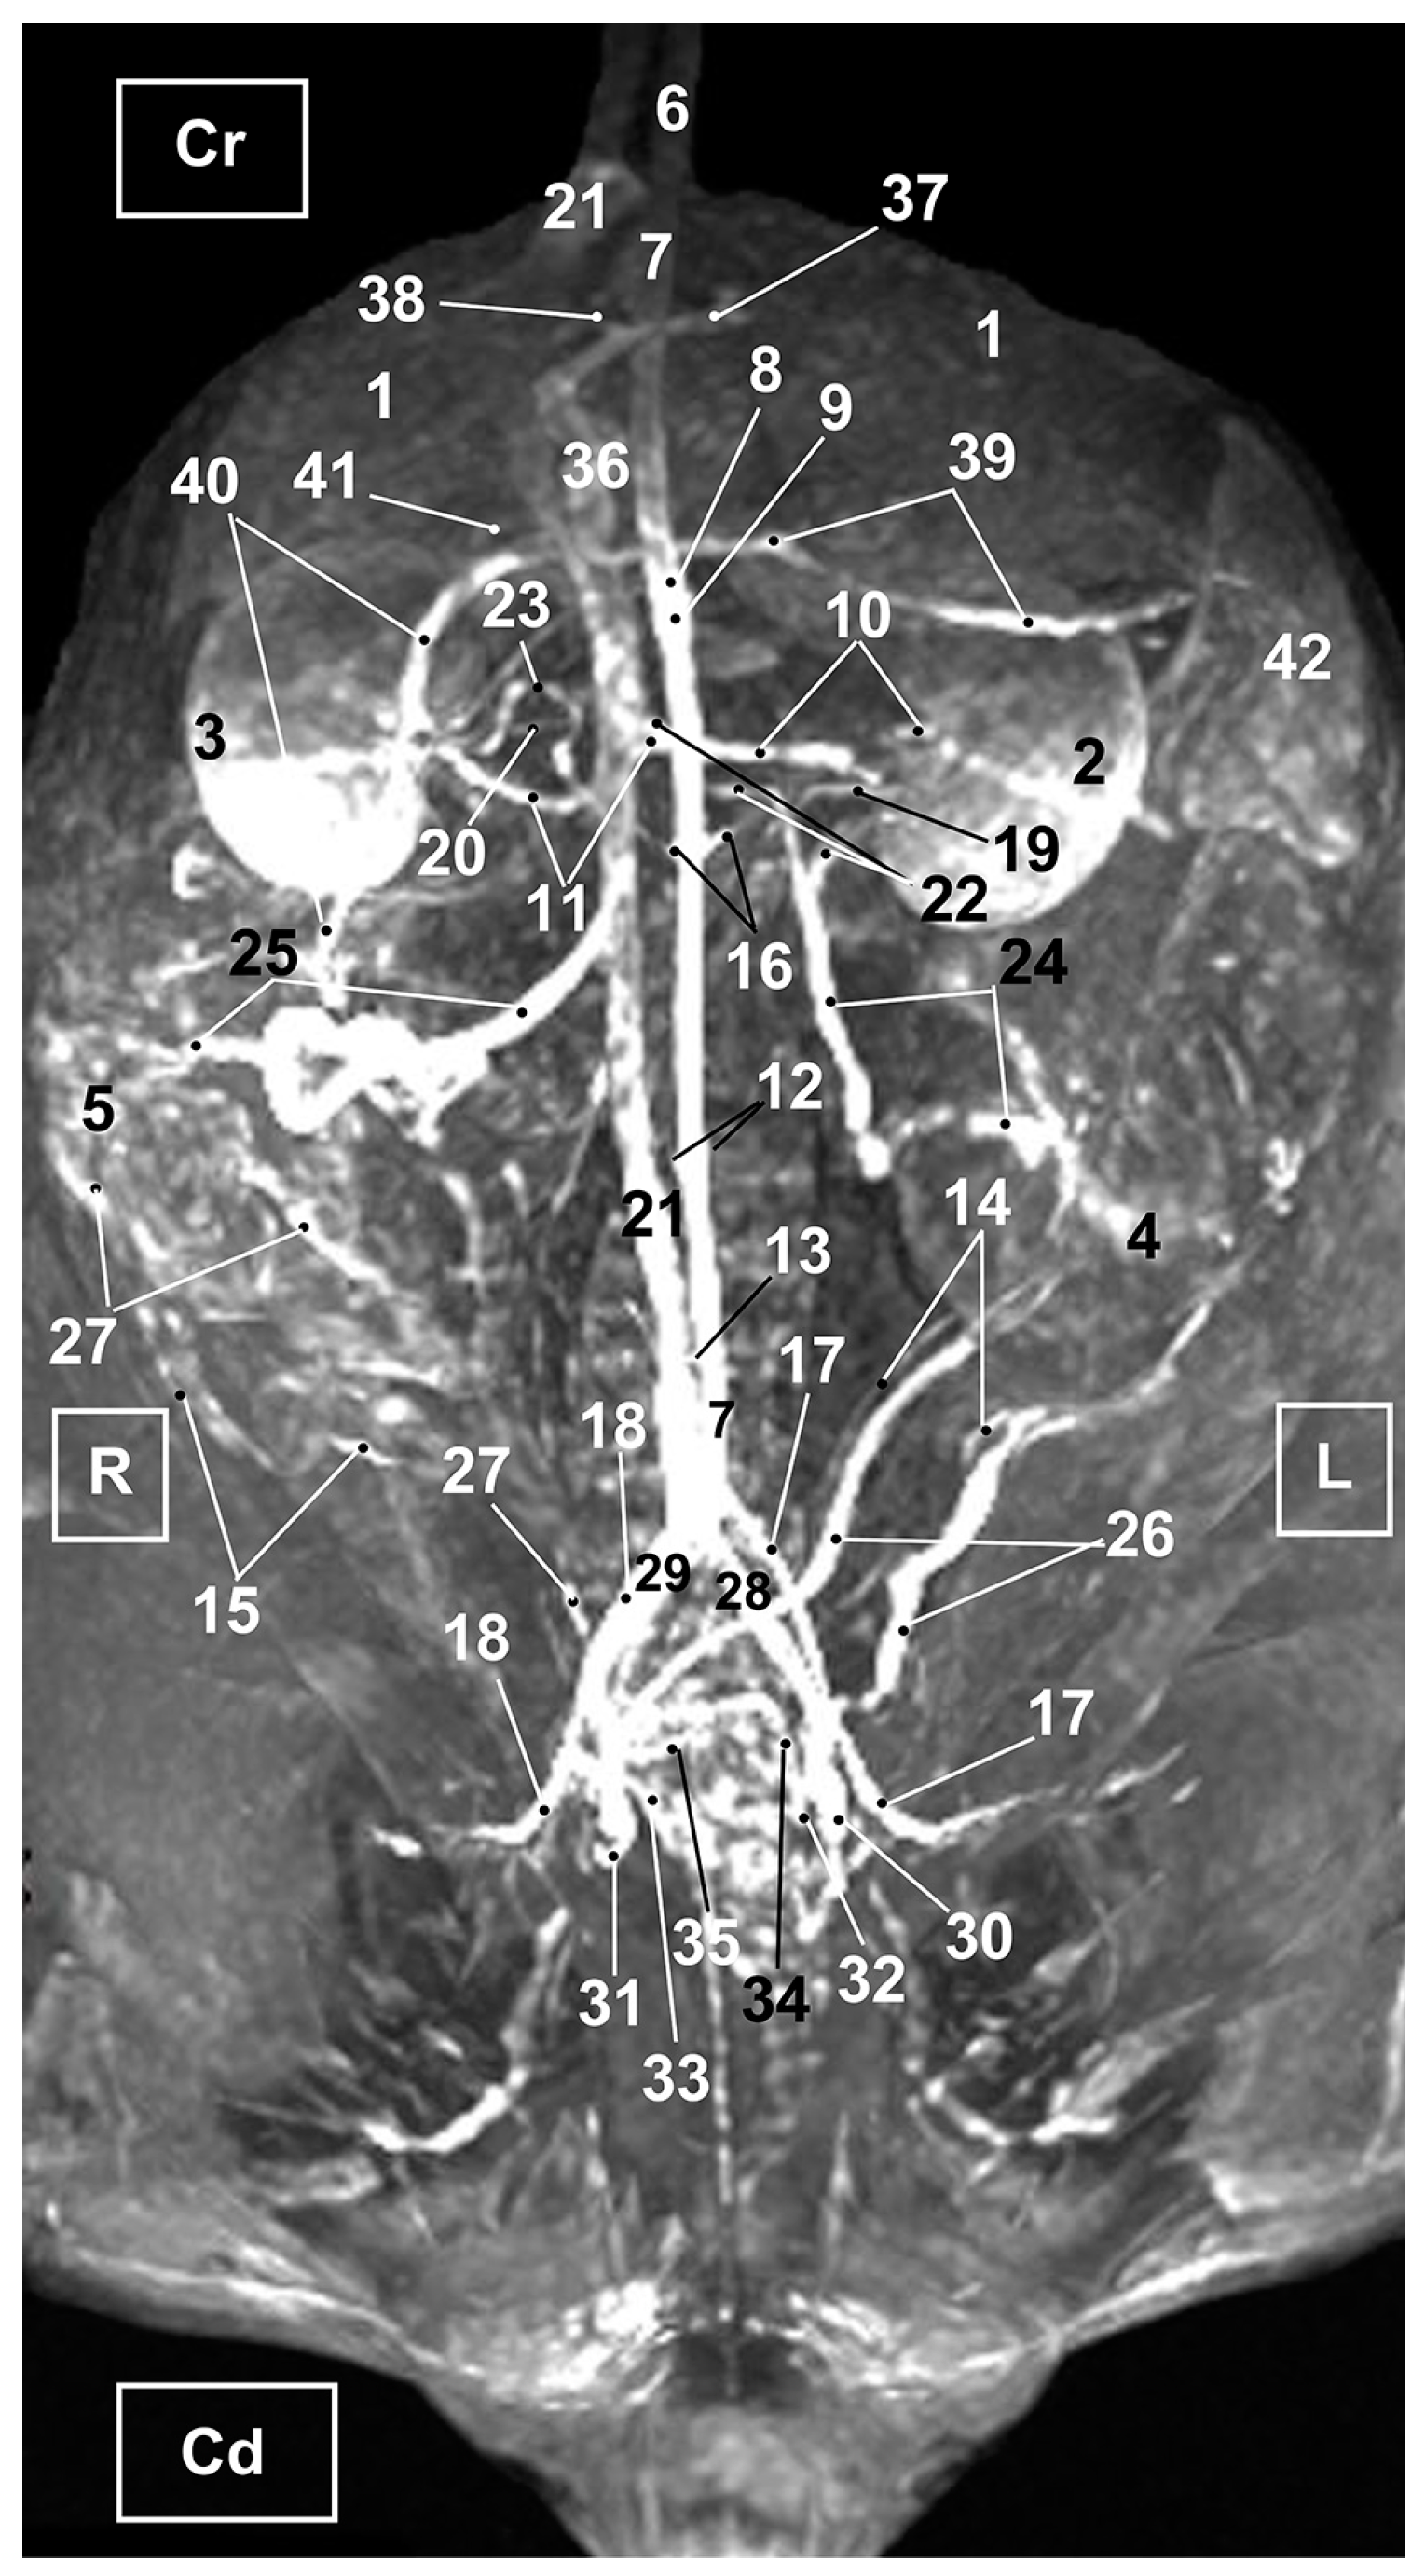

3.3. Magnetic Resonance Angiography

3.3.1. Arterial System

3.3.2. Venous System